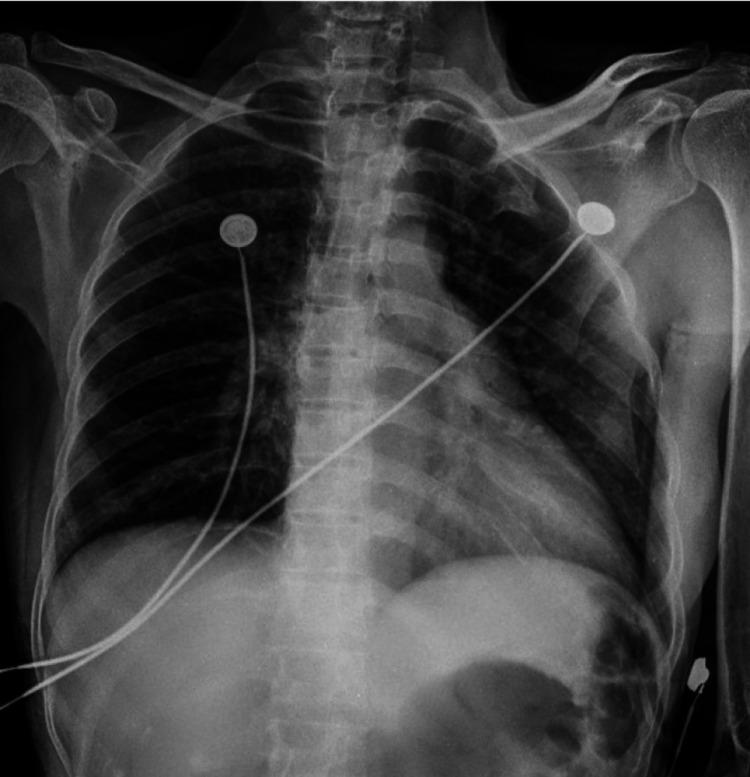

Scorpion stings are painful but harmless and are rarely life-threatening. There is emerging evidence of the association of electrocardiographic (ECG) changes in patients following scorpion stings. We report a case of scorpion sting in a patient in central rural India and provide a review of similar published cases. A 55-year-old previously healthy female was hospitalized in the department of medicine at our institute within two hours of a scorpion sting. She presented with severe pain at the site of the sting and profuse sweating. Her routine investigations (complete blood count renal function test, liver function tests, and arterial blood gas analysis) results were normal. Her electrocardiogram revealed acute myocardial infarction, and serial ECG showed ST and T-wave changes. On laboratory investigation, it was found that her troponin-T was positive and creatinine phosphokinase levels were raised. There was apical wall hypokinesia on transthoracic echocardiography on Day 1 and Day 2. The patient recovered completely and was discharged within five days of hospitalization once her symptoms improved. This case highlights the severe presentation of scorpion stings in otherwise healthy females. The chances of improved clinical symptoms are more if prazosin (125-250 ug) is administered early after scorpion-stung patients experience cardiac abnormalities. This treatment can dramatically alter scorpion envenomation's morbidity and mortality depending on the duration after which it is administered. This case raised our interest due to cardiovascular manifestations in the patient and the early treatment with prazosin for the scorpion sting. Hence, this case was reported for the purpose of creating awareness among physicians and protecting the more vulnerable population.

蝎子蜇伤虽会引起疼痛,但通常无害,很少危及生命。越来越多的证据表明,蝎子蜇伤患者会出现心电图(ECG)变化。我们报告了一例印度中部农村地区患者的蝎子蜇伤病例,并对已发表的类似病例进行了综述。一名55岁、此前健康的女性在被蝎子蜇伤后两小时内被收治于我院内科。她蜇伤部位剧痛且大汗淋漓。其常规检查(全血细胞计数、肾功能检查、肝功能检查和动脉血气分析)结果均正常。她的心电图显示急性心肌梗死,系列心电图显示ST段和T波改变。实验室检查发现她的肌钙蛋白T呈阳性,肌酸磷酸激酶水平升高。第1天和第2天经胸超声心动图显示心尖壁运动减弱。患者完全康复,症状改善后在住院五天内出院。该病例突出了蝎子蜇伤在原本健康女性中的严重表现。如果在蝎子蜇伤患者出现心脏异常后早期给予哌唑嗪(125 - 250微克),临床症状改善的可能性更大。这种治疗可根据给药时间显著改变蝎子蜇伤的发病率和死亡率。由于该患者的心血管表现以及早期使用哌唑嗪治疗蝎子蜇伤,此病例引起了我们的关注。因此,报告该病例旨在提高医生的认识并保护更易受影响的人群。